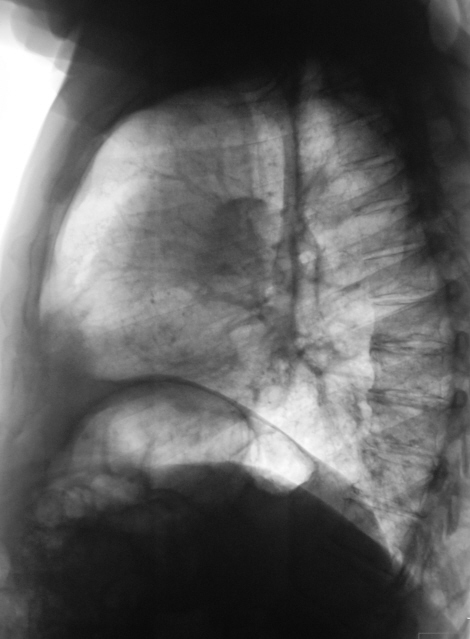

104.K.F..JPG

Сами знаете, Валентин Львович, к онкологам (картина периферичевого рака в/доли слева)... Кроме того, под подозрением л/узлы в правом корне и средостенье (КТ). Справа, думаю, старые переломы ребер...

Не исключено, что все изменения, которые видны в средостениии и левом корне - метастазы. Где первичная пока не ясно. Парез левого френикуса?

Согласен с Вами. Высоковат купол диафрагмы слева.